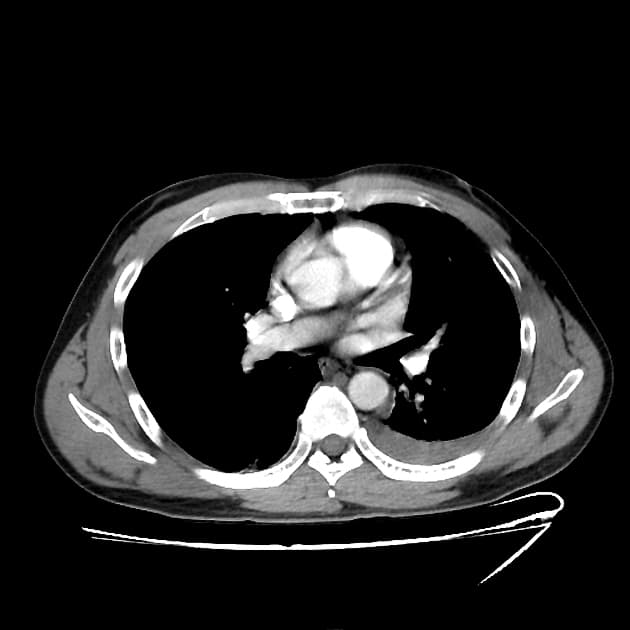

- Các nhánh đường mật trong gan (intrahepatic biliary radicles) giãn nhẹ.

- Ống mật chủ (common bile duct) giãn, thấy nhiều viên sỏi nhỏ có tín hiệu thấp ở đoạn cuối.

- Túi mật (gallbladder) căng giãn, chứa nhiều viên sỏi nhỏ.

- Tụy (pancreas) to lan tỏa và phù nề, xung quanh có dịch quanh tụy lan dọc theo các khe mỡ vùng sau phúc mạc, rõ hơn ở phía bên trái.

- Ống tụy (pancreatic duct) có vị trí, chiều dài và đường kính bình thường, cấu trúc bên trong đồng nhất, bờ trơn đều.

Sỏi túi mật (cholelithiasis) và sỏi ống mật chủ (choledocholithiasis) là những nguyên nhân phổ biến gây viêm tụy cấp (acute pancreatitis). Trong trường hợp này, viêm tụy cấp được phát hiện trên hình ảnh cộng hưởng từ đường mật tụy (MRCP) được thực hiện do có triệu chứng vàng da tắc mật và đau vùng thượng vị.

Viêm tụy cấp là một tình trạng lâm sàng phổ biến, thường do sỏi mật gây ra, đặc biệt khi chúng làm tắc ống mật chủ tại nhú tá lớn (ampulla of Vater). Trường hợp này cho thấy các hình ảnh điển hình trên MRCP bao gồm to toàn bộ tụy, dịch quanh tụy và dấu hiệu tắc nghẽn đường mật do sỏi ống mật chủ. Sự hiện diện của nhiều viên sỏi nhỏ ở đoạn cuối ống mật chủ xác nhận nguyên nhân bệnh. Chẩn đoán sớm bằng MRCP cho phép xử trí kịp thời, bao gồm nội soi mật tụy ngược dòng (ERCP) để lấy sỏi. Việc phân biệt viêm tụy cấp với các nguyên nhân khác gây đau bụng và vàng da như viêm đường mật hay ung thư tụy là rất quan trọng vì các bệnh này đòi hỏi can thiệp khác nhau.